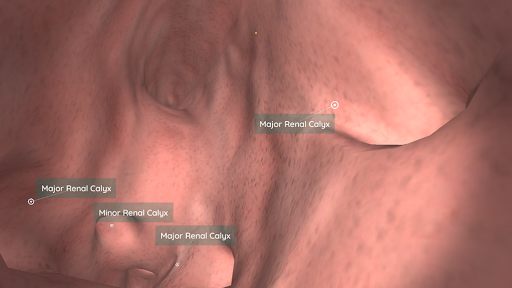

باستخدام الواقع الافتراضي ، سوف تكون قادرًا على التنقل على طول الهياكل التشريحية ، لتصبح جزءًا من علم التشريح البشري: الجهاز الدوري ، والجهاز التنفسي ، والجهاز الهضمي ، والبولي ، الدموي ، والإناث.

في وضع الواقع الافتراضي ، يجب إدراج الجهاز المحمول (الهاتف الذكي) في أداة الواقع الافتراضي للاستمتاع بتجربة غامرة بالكامل. يمكن للمستخدم التفاعل مع عناصر التحكم في التنقل وعناصر المعلومات التشريحية من خلال توجيهها.

على الرغم من أنه يوفر أفضل تجربة عند استخدامه في وضع الواقع الافتراضي ، إلا أنه يمكن للمستخدم الاستمتاع والتعلم مع تطبيق الهاتف المحمول هذا في وضع ملء الشاشة ، دون الحاجة إلى أداة الواقع الافتراضي.